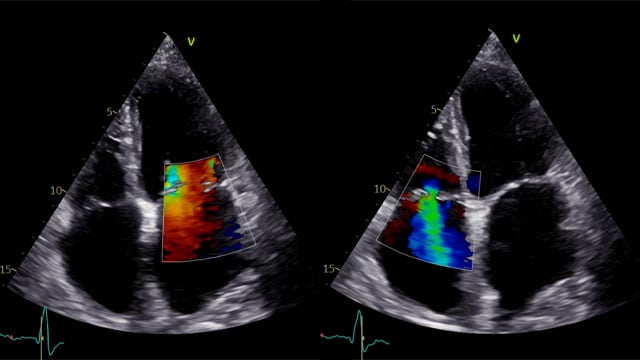

Severe MR in a high-risk patient with a suboptimal anatomy for M-TEER: what other options can we find?

Multimodality imaging reveals fibro-calcific leaflet disease, restricted motion, and a short posterior leaflet, making him a suboptimal candidate for M-TEER and prompting consideration of transcatheter mitral valve replacement. How would you treat?